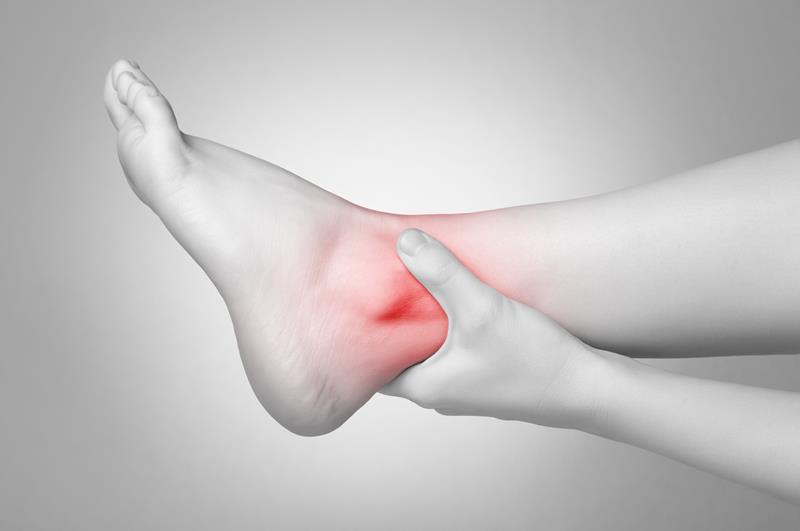

Sports Injury

Sports can be very taxing on your body, no matter what you play. Our trusted staff will work with you to get to the root of your problem and help you feel better again. We help treat and also prevent injuries in the neck, back, shoulders, knees, and ankles. We are able to manually adjust your spine, relieving any pain that you are feeling. This will allow your body to function much better after the injury.